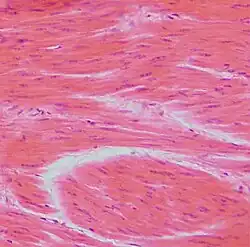

Dense Regular Connective Tissue

Parallel fibers of collagen. This connective tissue makes up ligaments and tendons

Smooth Muscle Cells